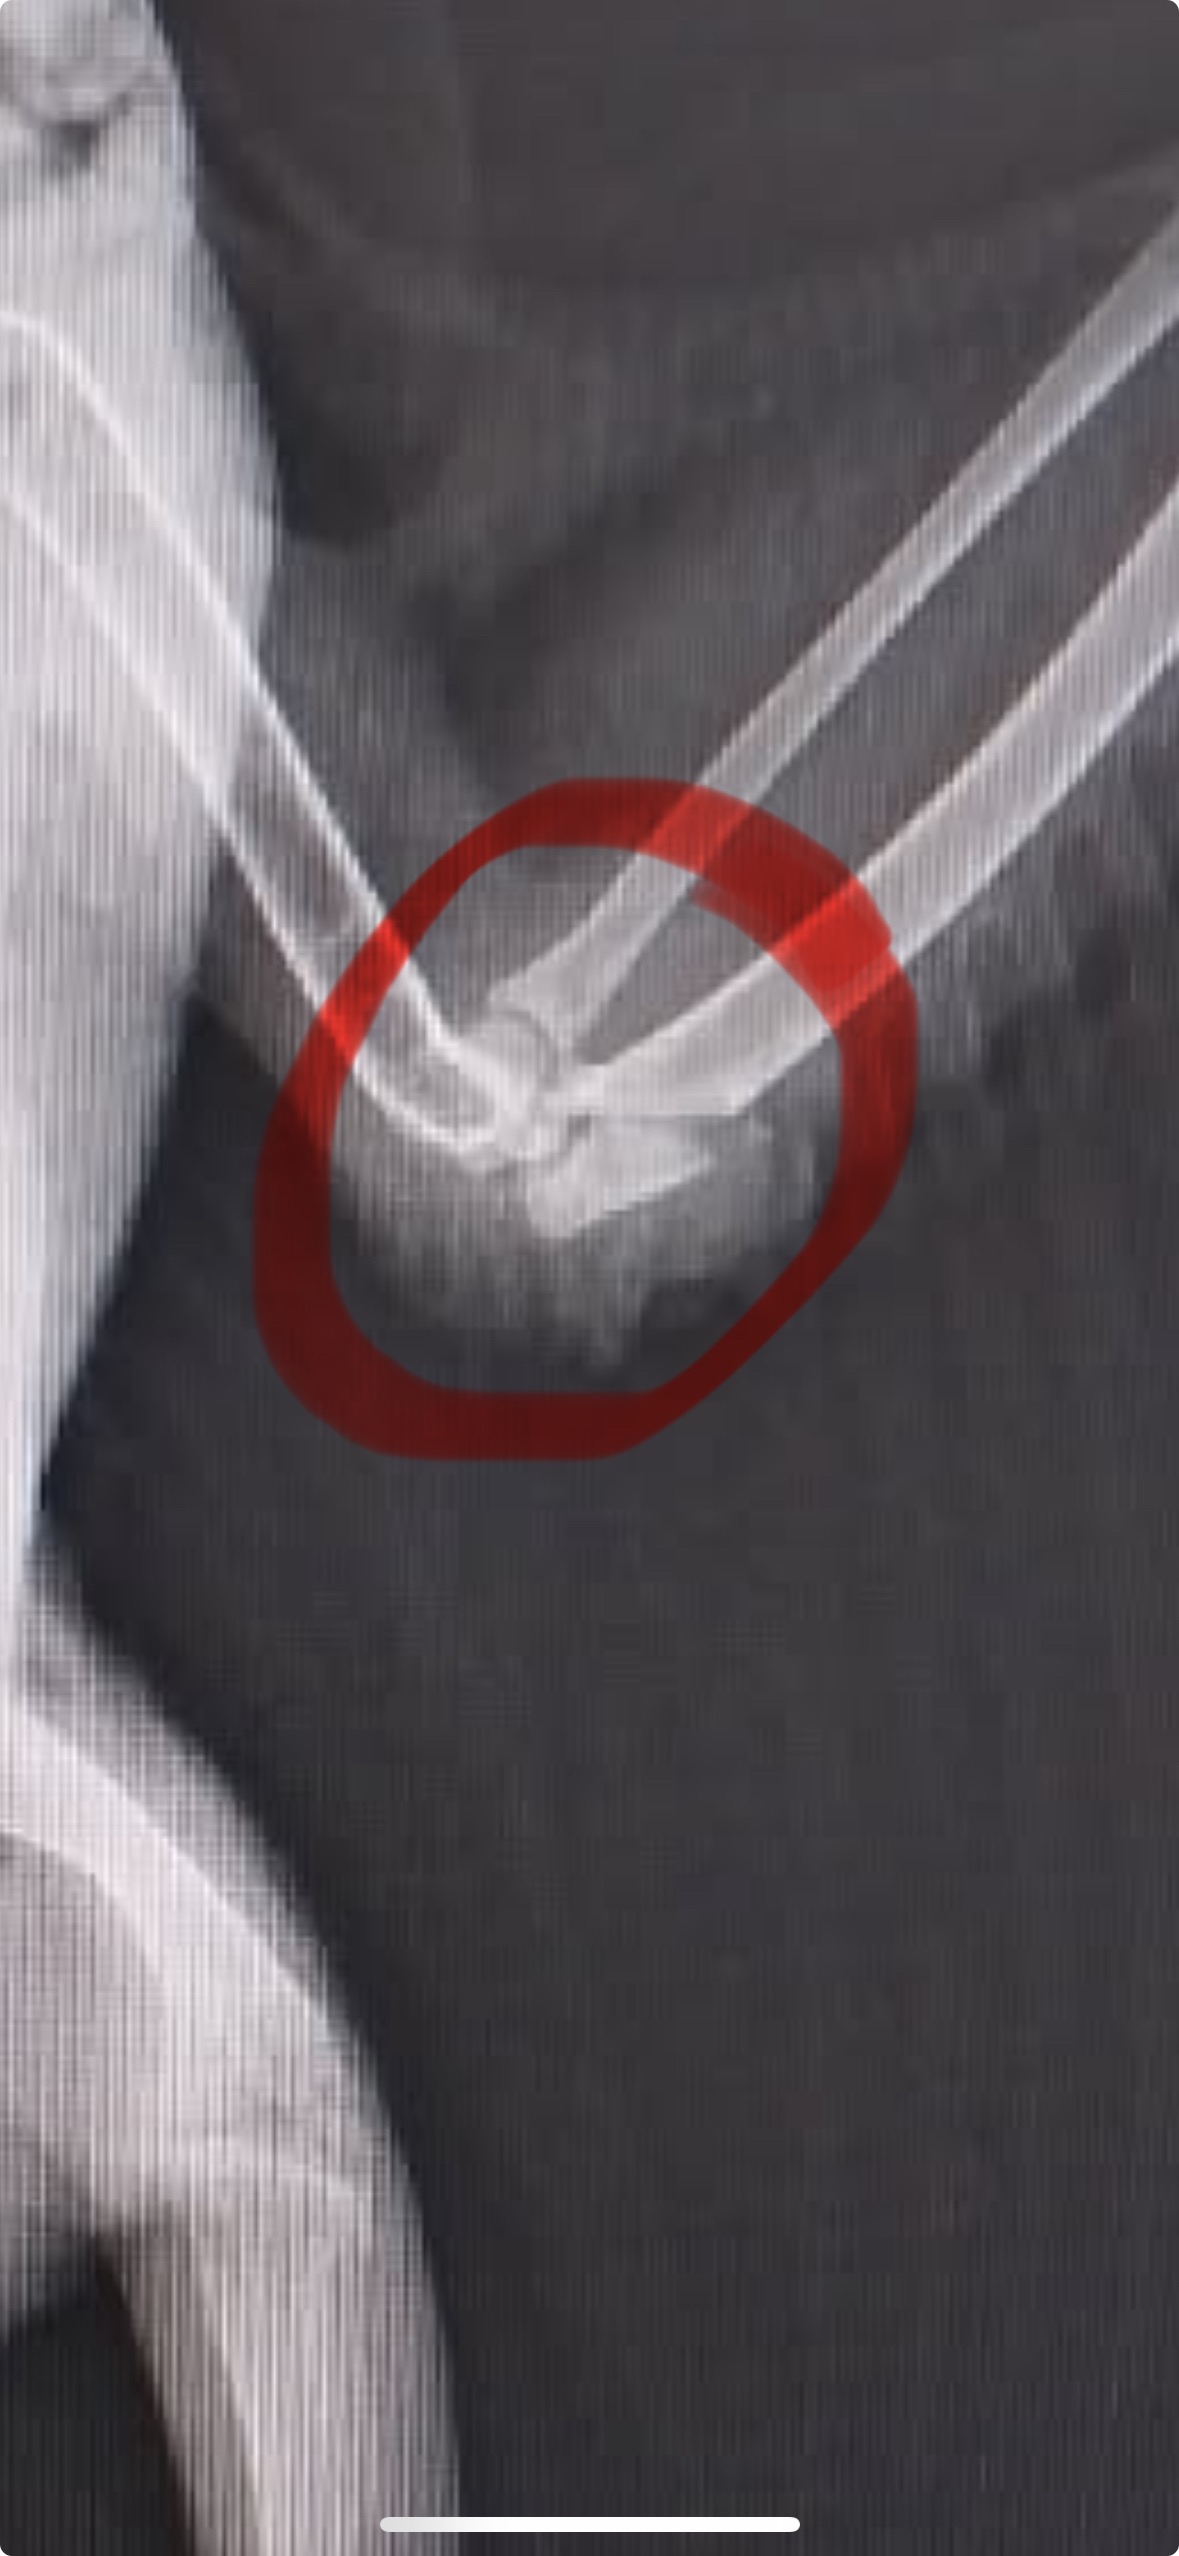

On the first day after her rescue, Margaret was terrified — she wouldn’t eat or drink, and just sat quietly in the corner. I knew she needed urgent help, so I took her to Dr. Nat at Campsie Vet. After an X-ray under anesthesia, we discovered her elbow was broken, most likely from a strong collision.